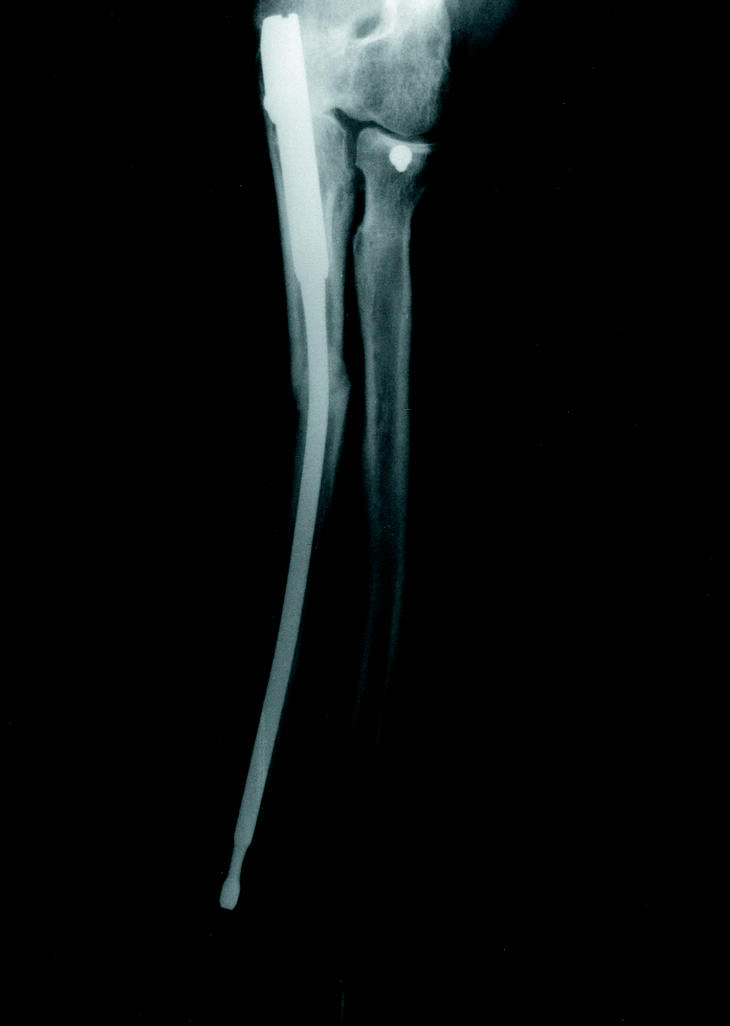

Ningún paciente fue inmovilizado durante el postoperatorio, iniciándose en todos una rehabilitación precoz. Todas las fracturas consolidaron; el inicio del callo osciló entre 1 y 3 meses (Fig. 4). La consolidación se obtuvo en un tiempo medio de 3,5 (mínimo 2,5 y máximo 5 meses) (tabla 1).

Figura 4. Rx postoperatoria a los 3 meses una vez lograda la consolidación. Se puede apreciar en la proyección de perfil una flexión de 120° y en la de frente una extensión completa.

La experiencia previa a esta serie hace que el periodo de aprendizaje de la técnica se haya obviado lo que permite obtener unos mejores resultados. Así, en ningún caso se ha inmovilizado el miembro, permitiendo, por otro lado, una rehabilitación precoz. La dosis de radiación intraoperatoria se ha reducido al mínimo y en la mayoría de los casos se ha procedido a la retirada del clavo una vez lograda la consolidación (Fig. 5), lo que es aconsejable en pacientes jóvenes ante la posibilidad de padecer un nuevo percance y en pacientes especialmente sensibles al roce en el codo.3-8

Figura 5. A los 6 meses se procedió a la retirada del clavo evidenciándose en el control postoperaoratorio el remodelado del callo de fractura. Rx AP.